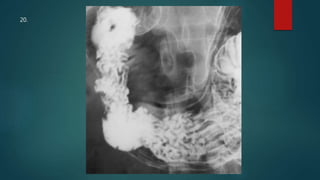

This document appears to be a medical report discussing several patients. It mentions a 35-year-old who was in a severe motor vehicle accident and an 81-year-old with a history of a non-vegetarian diet who had a perforated bowel from a chicken bone. The document provides few other details across its 25 numbered entries and was authored by Dr. Anish Choudhary for junior year 3 on May 30, 2016.